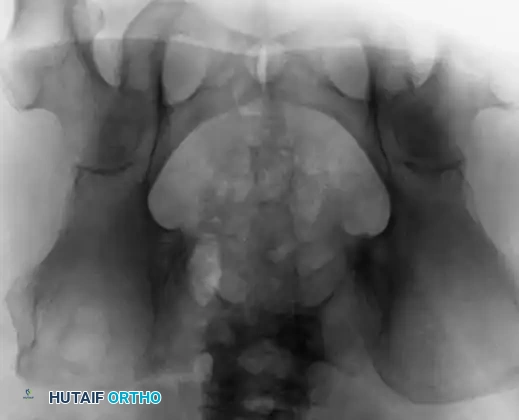

Fig. 22-11 A and B: Anteroposterior and lateral views of the sacrum of a patient with a sacrococcygeal chordoma. This lesion could be missed easily on the AP view because of overlying bowel gas.

Sacrococcygeal lesions are notoriously difficult to visualize on standard anteroposterior (AP) radiographs of the pelvis due to the superimposition of overlying bowel gas and fecal matter. They are usually seen much more clearly on a dedicated lateral view of the sacrum, which may demonstrate cortical destruction, anterior displacement of the presacral soft tissues, or a calcified mass.